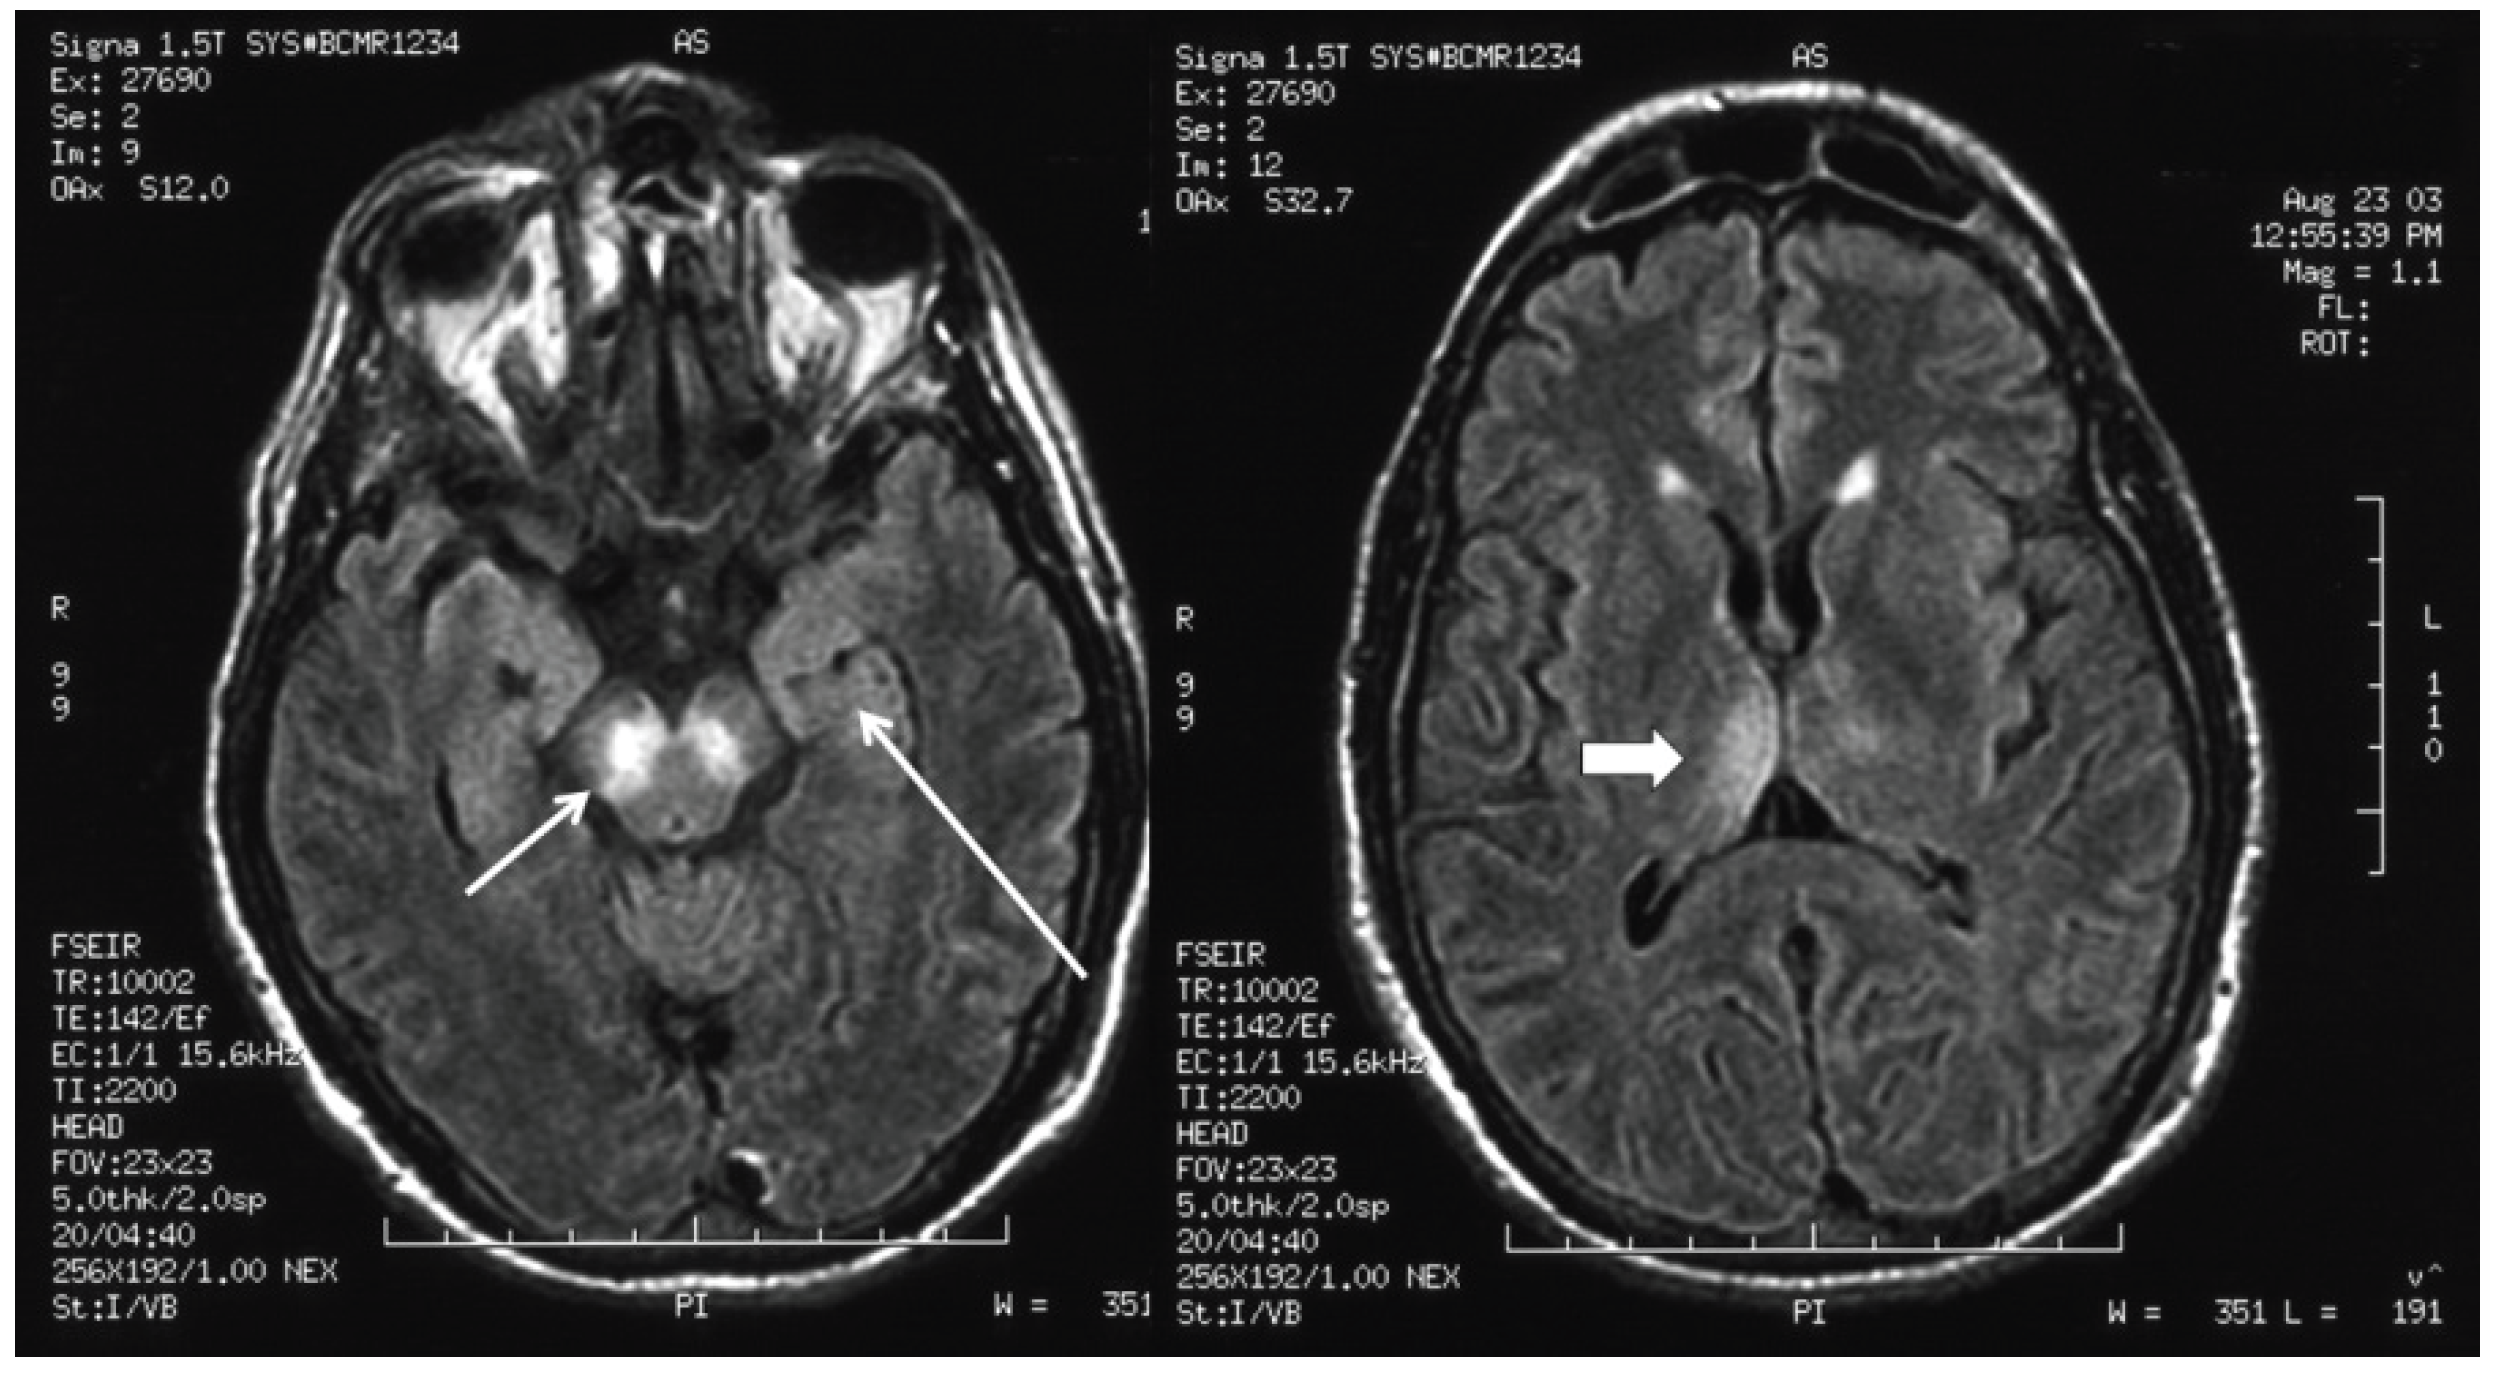

The development of these movement disorders in WNE is due to specific neurotropism of WNV for extrapyramidal structures; there is frequent involvement of the brainstem (particularly, the medulla and pons), the deep gray matter nuclei, particularly the substantia nigra of the basal ganglia and the thalami, and the cerebellum [25,26,27]. This clinico-pathologic correlation may be extended to the neuroimaging abnormalities seen in West Nile encephalitis.

The estimated proportion of patients with WNE who demonstrate abnormal findings in brain magnetic resonance imaging (MRI) varies considerably between studies; however, MRI findings are not ubiquitous, and even in cases of severe WNE, the MRI may be normal; or abnormal findings may not be apparent until several weeks after the onset of illness [28,29,30]. The most characteristic MRI findings in patients with WNE are bilateral signal abnormalities in the basal ganglia and thalami on T2- , fluid-attenuated inversion recovery (FLAIR) and diffusion-weighted image sequences, indicating the viral neurotropism for these deep gray structures (Figure 2). These MRI findings, which may be seen in other flaviviral encephalitides, including encephalitis, due to Japanese encephalitis virus and St. Louis encephalitis virus, may be indicative, but not diagnostic for, WNE. Electroencephalographic (EEG) abnormalities may be present in the form of generalized slowing, frequently anteriorly or temporally predominant, and triphasic sharp waves [31,32]. These EEG abnormalities, however, are also nonspecific. Overt seizures appear to be relatively uncommon with WNE and are estimated to occur in 3%–6% of patients [33]. Similarly, increased intracranial pressure and cerebral edema appear to be uncommon in WNE. CSF abnormalities in patients with WNE are essentially the same as those seen in WNM, characterized by moderate lymphocytic pleocytosis, elevated protein and normal glucose. One large study suggested that the mean CSF white blood cell count in patients with WNE was 227 cells/mm3 (median, 90 cells/mm3) [34].

Figure 2. Fluid-attenuated inversion recovery magnetic resonance imaging sequence of the brain in a patient with West Nile virus encephalitis with associated parkinsonism and tremor, displaying signal abnormality in the substantia nigra (short arrow), the mesial temporal lobe (long arrow) and right posterior thalamus (thick arrow).